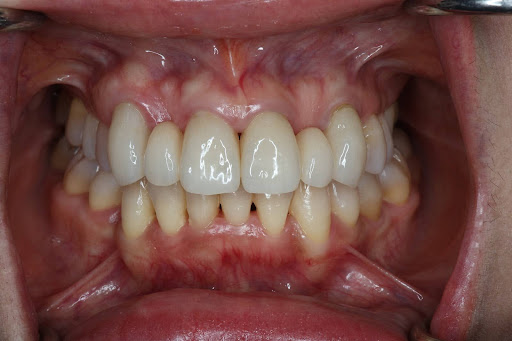

削らず、美しく整える “矯正 × セラミック治療” の治療選択肢

「歯をあまり削りたくない」「でも見た目も整えたい」そんな方のために、矯正とセラミック治療を組み合わせた方法です。先に歯並びを整えることで、必要以上に削らず、自然でキレイな見た目に仕上げることができます。噛み合わせも良くなるため、治療も長持ちしやすいのが特徴です。

このような方に、当院の矯正×セラミック治療のハイブリッド治療は特におすすめです。